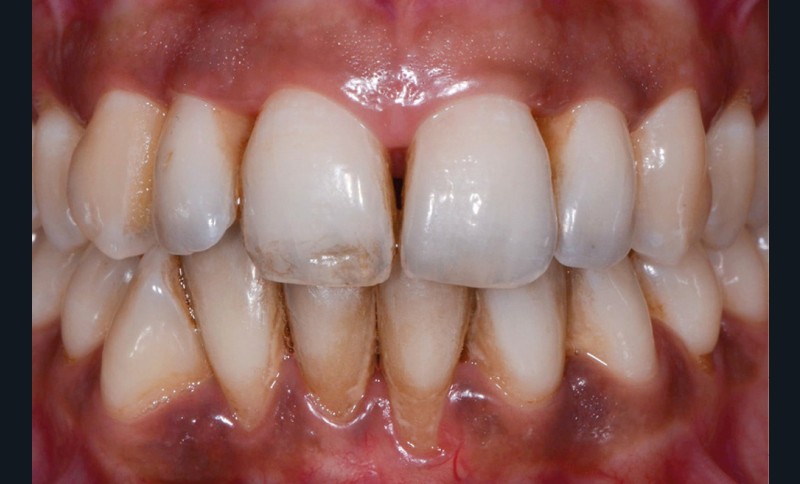

Elles sont causées par des agents colorants externes qui se déposent généralement sur la surface amélaire. Leurs origines sont diverses : alimentation (fig. 1b), tabac (fig. 1c), plaque bactérienne ou bactéries chromogènes (fig. 1d), ainsi que certains médicaments. La réalisation d’un aéropolissage en complément du détartrage initial est généralement suffisante pour éliminer efficacement ces colorations. Cependant, le patient doit être prévenu qu’en l’absence de modification de ses habitudes de vie, celles-ci reviendront [2, 4].